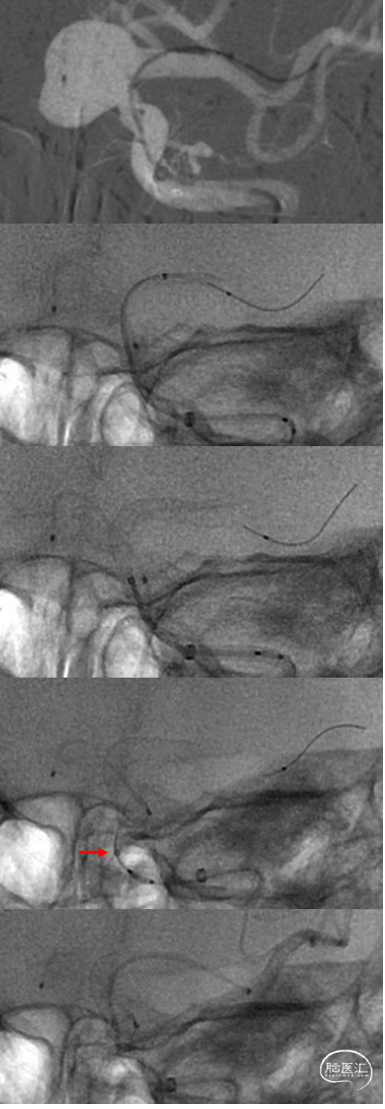

8F导引导管置于颈总动脉,6F中间导管到达岩骨段。Synchro 14导丝超选动脉瘤远端,到达M2上干,XT-27顺利跟随到M2上干平直段。瘤内预置17微导管备用。

①XT-27导管到位后送入支架,推送阻力较小,过瘤颈时未出现疝入瘤腔的征象,②头端导丝较短,显影段后部可见标记支架头端的mark点,释放后支架头端轻微短缩,位于mark点近端约5mm;该支架头端用于保护的“小翅膀”短而细,不影响支架头端展开,头端采用撤管的减张力释放方式即可,③头端减张释放10mm左右后支架前端基本贴壁,此时予以增加张力确保头端锚定,过瘤颈时继续采用低张力释放,避免支架过多疝入瘤腔,通过后可再增加张力以保证支架贴壁;④整个过程不需要给予很高的张力,在释放至尾端时,可见到XT-27头端(红箭)、支架回收点和支架尾端三个mark形成的等距“三点征”,此时应释放推送的张力,后撤XT-27完全释放支架;⑤完全释放后跟进XT-27导管至支架远端。

再次造影观察瘤内造影剂滞留较支架释放前明显。栓塞4个弹簧圈,直⾄瘤腔内显影明显减少,⽆显著滞留后结束栓塞,术后造影为Raymond 3A,OKM A3级。